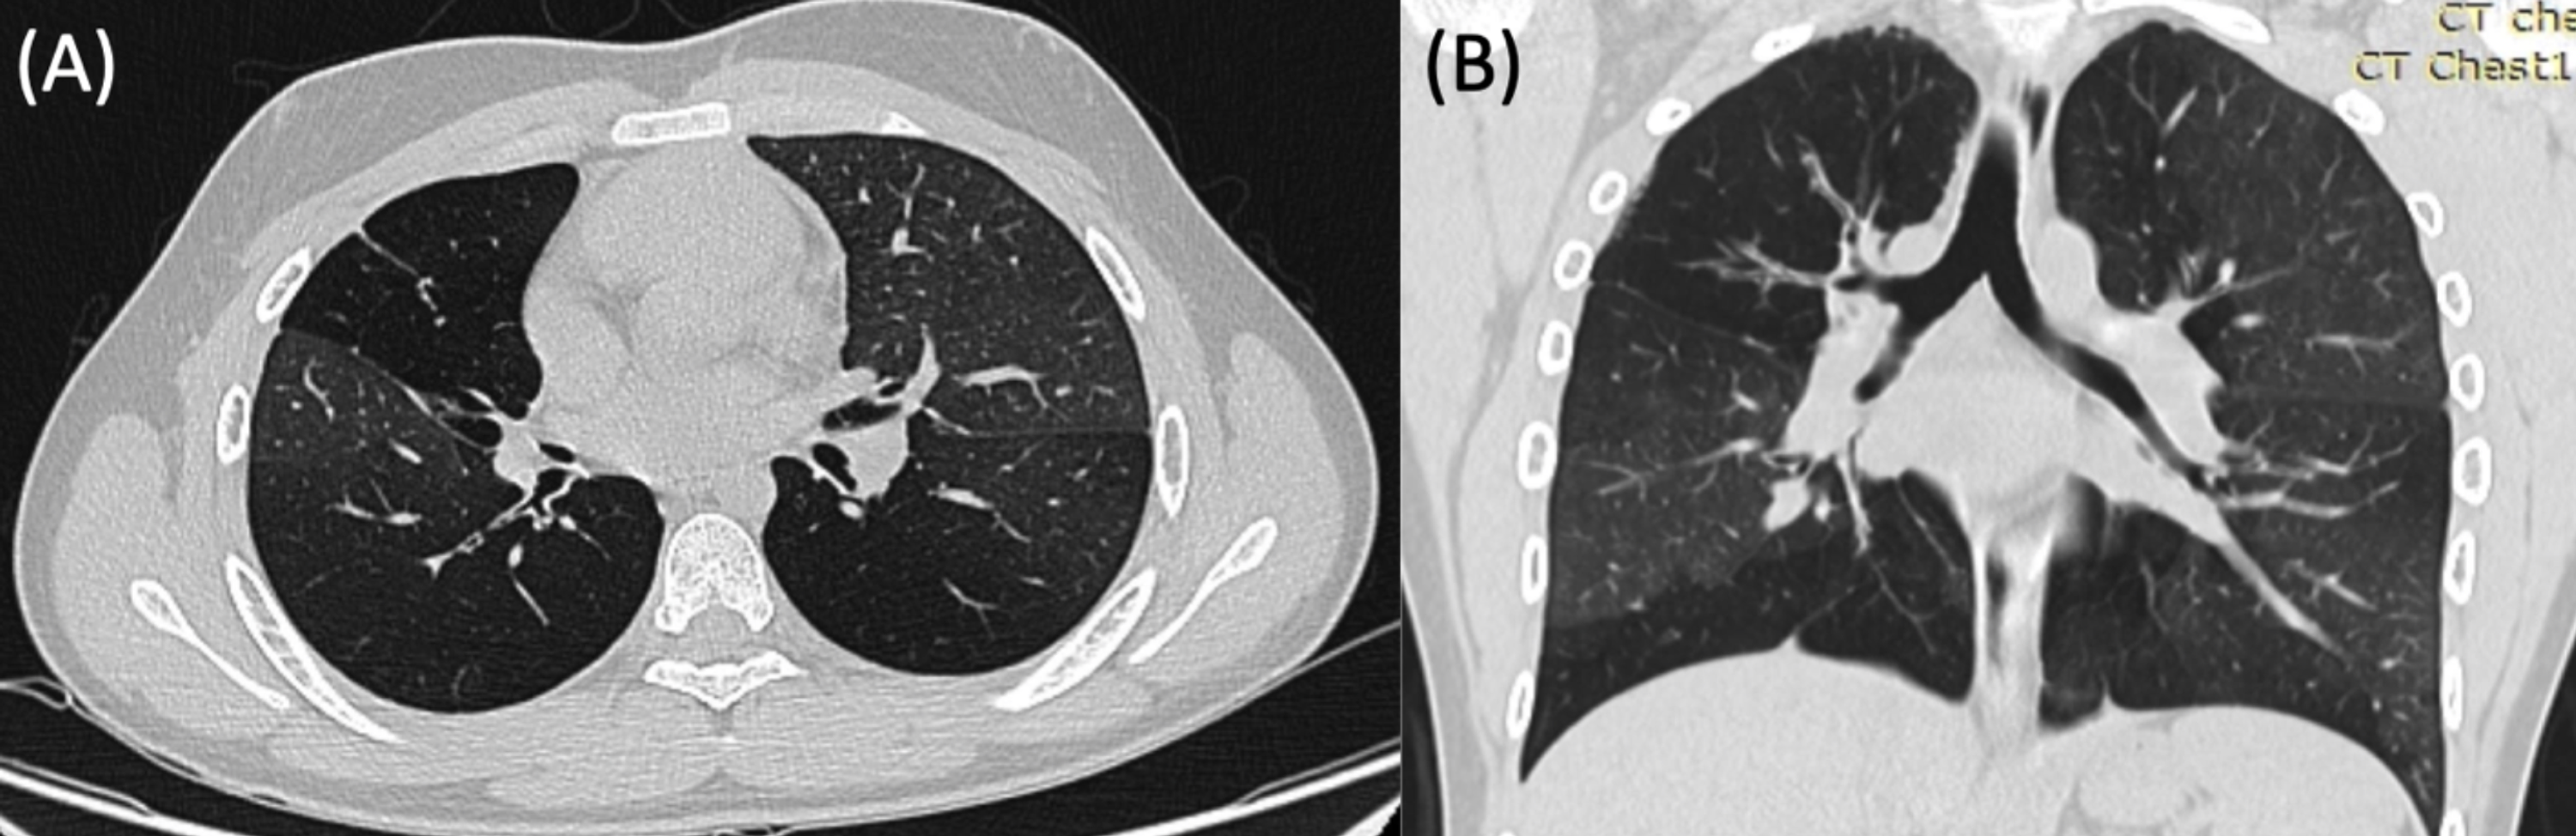

Figure 1 from Acute respiratory distress syndrome related to Mycoplasma Acute Bronchitis Due To Mycoplasma Pneumoniae Bacteria called mycoplasma pneumoniae can cause respiratory tract infections. While the cough is initially dry, it may later produce moderate amounts of. Mycoplasma pneumoniae are a common cause of bacterial respiratory infections. It usually causes upper respiratory tract infections but can also cause pneumonia, and it is one of the most. In addition to tracheobronchitis symptoms, pneumonia symptoms can include. Acute Bronchitis Due To Mycoplasma Pneumoniae.

Figure 1 from Acute Respiratory Distress Syndrome due to Mycoplasma Acute Bronchitis Due To Mycoplasma Pneumoniae Mycoplasma pneumoniae are a common cause of bacterial respiratory infections. It usually causes upper respiratory tract infections but can also cause pneumonia, and it is one of the most. In addition to tracheobronchitis symptoms, pneumonia symptoms can include mild dyspnea. M pneumoniae is the main human pathogen species of this group and causes respiratory infections including upper respiratory tract infection,. Acute Bronchitis Due To Mycoplasma Pneumoniae.